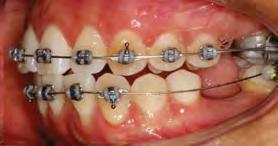

52 | SONRIENDO AL FUTURO

Tratamiento ortodóncico en paciente adulto tratado con extracciones de primeros molares permanentes. Reporte de caso

Tratamiento ortodóncico

en paciente adulto tratado con extracciones de primeros molares permanentes. Reporte de caso